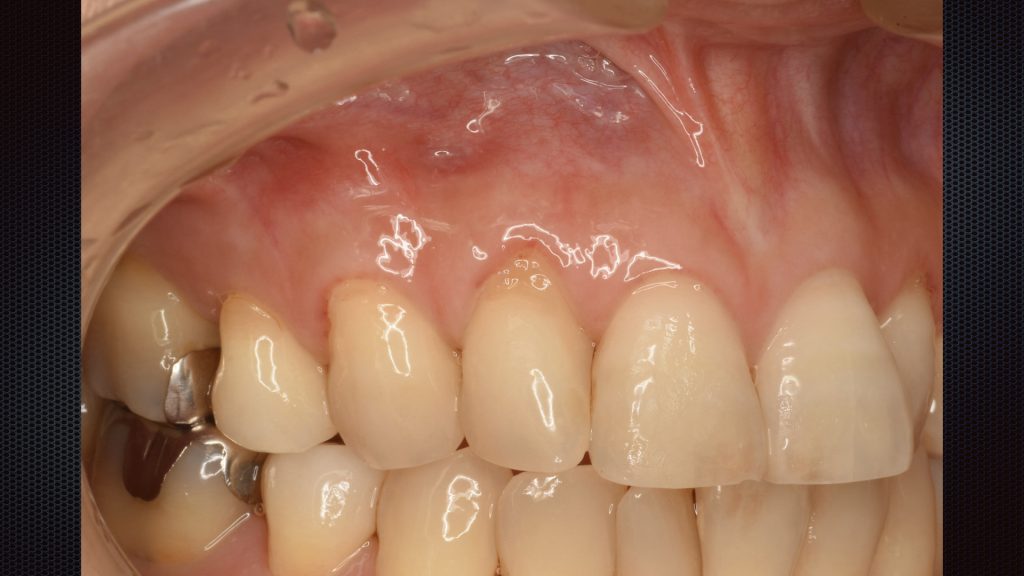

⬇︎術直後の口腔内写真です。

結合組織を歯肉で覆い被せるように縫合を行っています。